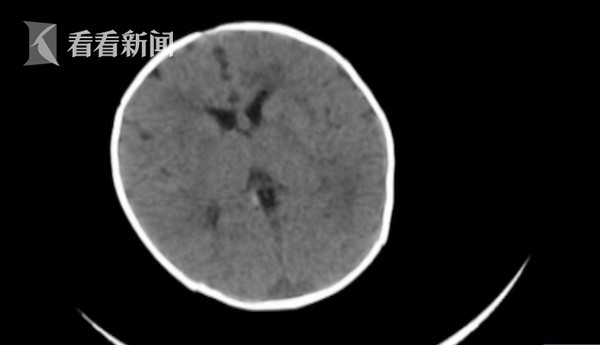

Bác sĩ Nhi khoa Đại Liên tại Bệnh viện Nhân dân thành phố Thanh Viễn đã cho tiến hành chụp CT và phát hiện có xuất huyết não một ít trong não. Qua các xét nghiệm, bác sĩ nhận thấy chức năng đông máu của bé gái này không tốt, điều đó có nghĩa là cô bé đang bị thiếu vitamin K. Sau khi điều trị, tình trạng của cô bé được cải thiện.